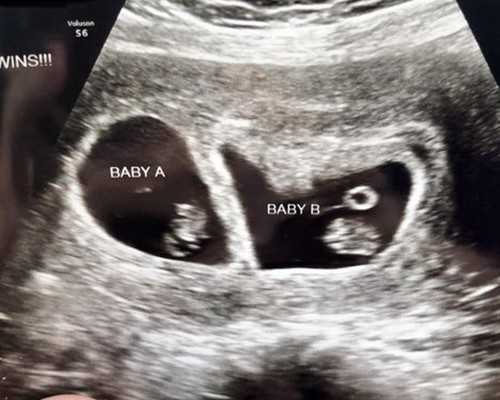

2022年,国内失独家庭一般可一次性领取不超过3万元的再生育补贴。通过人工授精技术怀孕一般为2000元,试管婴儿技术怀孕一次性补贴2-3万元。当然,不同地区的政策要求也有所不同,具体事宜应咨询当地计划生育办公室。

2、辅助生殖补贴:对愿意再生育的计划生育特殊困难家庭夫妇,如果女性年满35岁并且需要实施辅助生殖技术的,给予不超过3万元的再生育补贴;

2.生殖救助:具备生育条件的家庭可享受生殖救助政策,辅助生殖费用可减免;